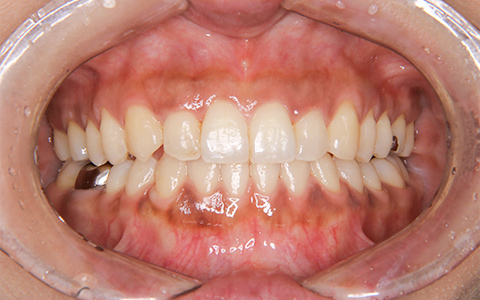

治療前

治療後

施術内容 上の2番目の歯が内側にあることがお悩みでご来院(33歳)。前歯部の叢生・交叉咬合に対するマウスピース型矯正装置(インビザライン)による非抜歯治療

治療期間 1年1ヶ月(通院7回)

費用 880,000円

リスク・副作用 歯が動く痛み、歯髄壊死、歯根吸収、歯肉退縮、リテーナーを使用しないことによる後戻り